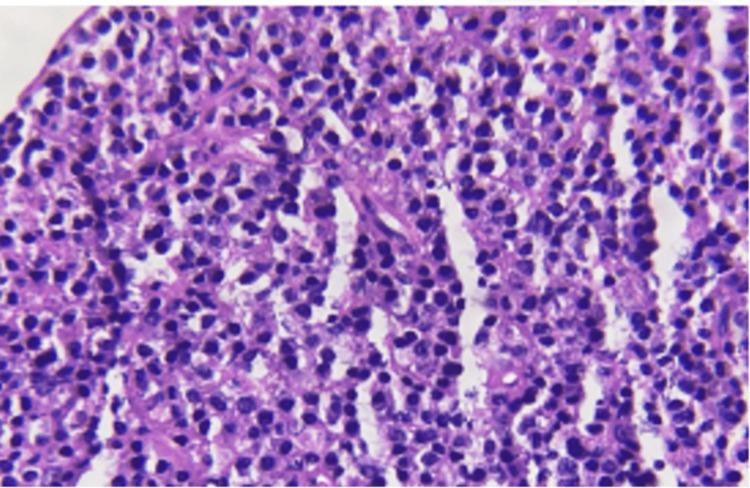

In a clinical context, oral lymphomas are very uncommon and frequently challenging to identify. Mucosa-associated lymphoid tissue (MALT) lymphomas are a diverse category of lymphomas that were formerly believed to be formed from B-cells located in the marginal zone, which surrounds B-cell follicles and the surrounding lymphoepithelium. Extranodal organs like the stomach, thyroid, and large salivary glands are where they most frequently appear. As a result, they are accurately identified as extranodal marginal zone B-cell lymphomas (ENMZL). This report presents a case of a 53-year-old female with lower lip swelling, which was diagnosed as a case of marginal low-grade B-cell non-Hodgkin's lymphoma after clinical, histopathological, and immunological examinations. Non-Hodgkin's lymphoma diagnosis can be aided by pathological examination and biopsy performed early in the lesion's development. The dentist has a key role to play in the early diagnosis process.

在临床环境中,口腔淋巴瘤非常罕见,且识别起来常常具有挑战性。黏膜相关淋巴组织(MALT)淋巴瘤是一类多样的淋巴瘤,以前被认为是由位于边缘区的B细胞形成的,边缘区围绕着B细胞滤泡和周围的淋巴上皮。它们最常出现在胃、甲状腺和大唾液腺等结外器官。因此,它们被准确地识别为结外边缘区B细胞淋巴瘤(ENMZL)。本报告介绍了一例53岁女性下唇肿胀的病例,经临床、组织病理学和免疫学检查后,被诊断为边缘性低级别B细胞非霍奇金淋巴瘤。在病变发展早期进行病理检查和活检有助于非霍奇金淋巴瘤的诊断。牙医在早期诊断过程中起着关键作用。